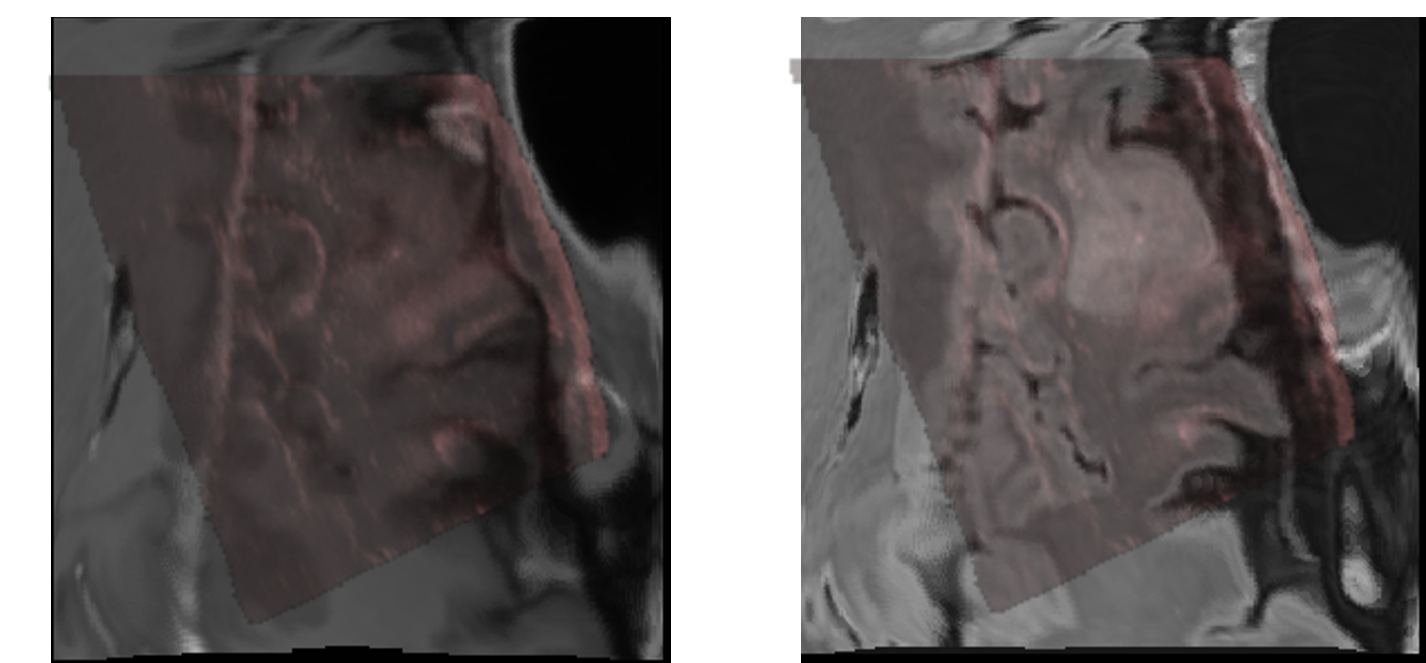

Figure 4: Visualization result of MRI-US fusion for the large deformation case before (left) and after (right) registration using MCPO-deform.

Since the ReMIND2Reg Sub-challenge includes only five patients (ten cases) with annotation information as the validation set with all exhibiting relatively small deformations, validation based solely on this dataset may lead to potential overfitting to a limited number of similar data, making it difficult to comprehensively evaluate the performance of the methods. Therefore, we conducted additional experiments on the Resect dataset, with results presented in Table 2. On this more diverse dataset, MCPO-deform achieved superior average TRE of 1.798 ±\pm 1.301 mm, while other methods often failed to handle cases with large deformations effectively. As illustrated in Fig. 3, which shows a case from the Resect dataset with an initial deformation of 19.731 mm, MCPO-deform successfully aligned key anatomical regions between the fixed and warped images. For this case, MCPO-deform achieved registration errors of 1.136 mm (FLAIR to ultrasound) and 1.368 mm (ceT1 to ultrasound). In comparison, MCPO-rigid only reached 13.313 mm and 16.195 mm, respectively. The visulization result for this case is shown in Fig. 4. Considering these results, we ultimately submitted MCPO-deform as the Docker for the testing phase of the ReMIND2Reg sub-challenge.